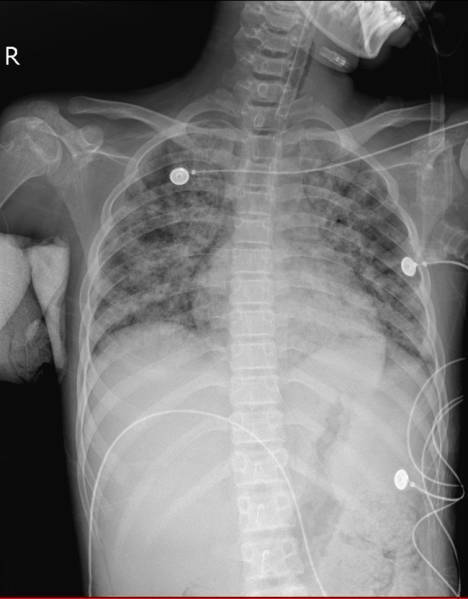

患儿治疗后胸片

确定治疗方向后,由于病情急剧进展,患儿于入院第三天转入ICU治疗。在呼吸机给予100%纯氧的情况下,患儿病情依然危重,床旁胸片显示患儿肺部感染十分严重。联合院内体外循环,儿科,胸外,心外科多科室专家,ICU刘主任与各位专家认为患儿具备ECMO指征。运用经皮穿刺技术为患儿应用“人工肺”,机器运转后,患儿的血氧饱和度迅速上升至97%,效果显著。

检索万方和知网,目前国内无耶氏肺孢子虫肺炎接受ECMO治疗的报道。重症医学科治疗及护理团队面临严峻挑战。患儿患病期间ICU团队与体外循环团队紧密合作,针对患儿的病情变化不间断的调整治疗方案,患儿在运用“人工肺”9天之后成功下机,肺部感染情况有了非常大的改善。15天后脱离危险,转回普通病房继续治疗,目前没有气促,不需氧疗,体温正常,生活能够自理,之后痊愈出院。